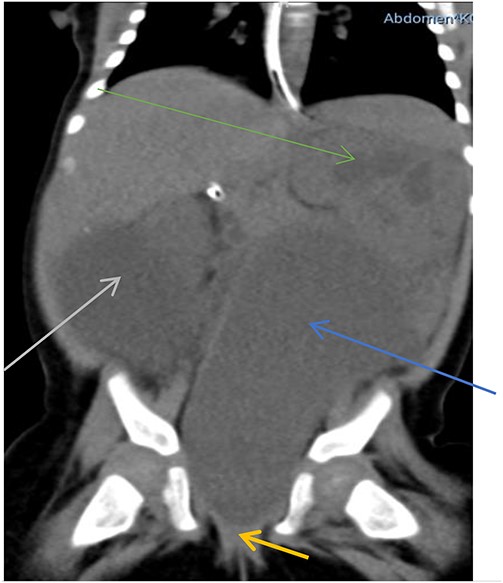

Abdominal X-RAY both supine and erect revealed a soft tissue mass involving the lower quadrant of the abdomen. However, there was no sign of intestinal obstruction. Abdominopelvic ultrasound showed a large, well-defined, anechoic intra-abdominal mass measuring 12 cm × 6 cm, bilateral moderate hydronephrosis and a thick-walled urinary bladder. The uterus could not be appreciated but ovaries were normal. Computed tomography (CT) revealed a centrally located hypodense cystic mass arising from the uterus connected to the upper vagina, located between the urinary bladder and rectum, measuring 7.6 cm × 3.5 cm × 4.6 cm. The mass was extending to the upper abdomen, abutting the rectum and pushing the urinary bladder to the right causing bilateral moderate hydroureteronephrosis (Fig. 1).

Hypodense mass arising from the uterus (blue arrow), connected to the upper vagina (yellow arrow) pushing the urinary bladder to the right (grey arrow) associated with hydronephrosis (green arrow).